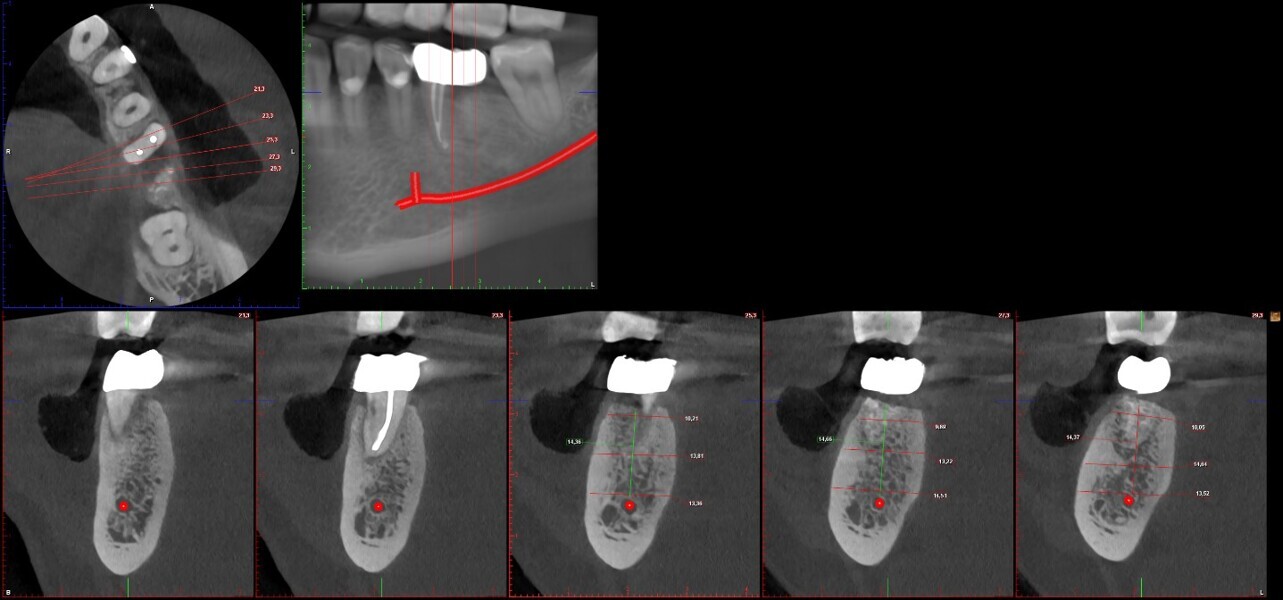

One year later, the restoration was performing well and the patient was asymptomatic. Radiographs and a CBCT control scan showed complete bone healing. On the periapical radiograph, the tooth showed a healthy periodontal ligament and no signs of failure in the restoration (Fig. 12). The cross-sectional, axial and coronal views of the CBCT scan showed good bone width and height and no pathological findings (Figs. 13–16). The oclusal scans and clinical images showed good adaptation of the new restoration and a healthy gingiva (Figs. 17–20).